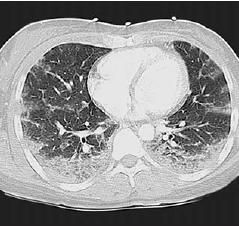

A chest radiograph showed bilateral alveolar infiltrates with peripheral predominance in both lungs (Figure 1). A CT scan of the chest showed extensive alveolitis, with lobular ground-glass opacities and thickening of the interlobular septa (Figure 2). The patient was found to have eosinophilia with an absolute eosinophil count of 750/μL, which amounted to 7% of her peripheral white blood cell count.

Figure 2 – Extensive alveolitis is present on this chest CT scan. Additional findings include lobular ground-glass opacities and thickening of the interlobular septa.